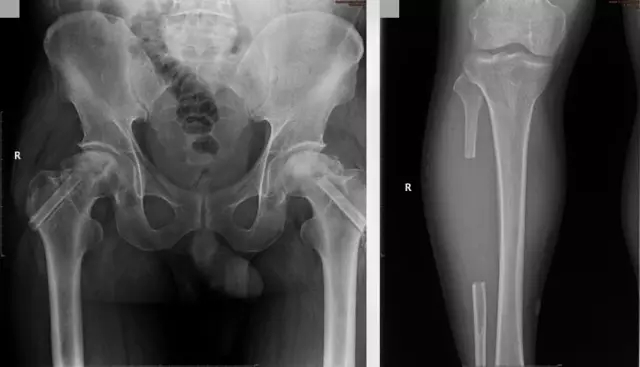

2016年5月,王某右髋疼痛完全缓解,他再一次来到我院关节·足踝组进行了左髋手术治疗,恢复情况良好。对于专家们的精心救治,王某心中有说不出的感谢。

第二次术后复查X线